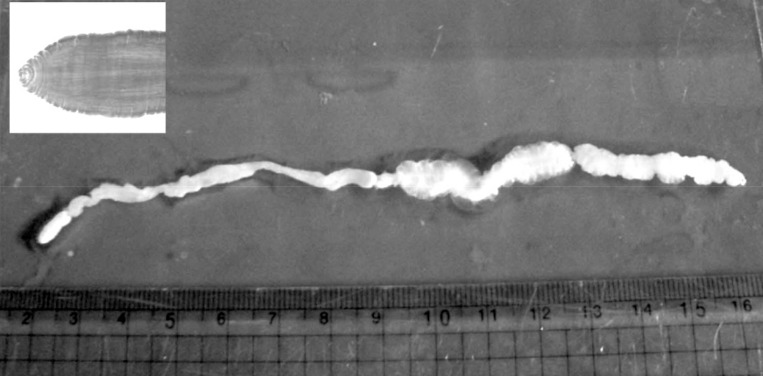

Routine laboratory tests were unremarkable, and no eosinophilia was noted. Ultrasonography (USG) showed diffuse longitudinal (about 10 cm) thickening of the subcutaneous fat layer with increased echogenicity on the lateral aspect of the right fibula (

Fig. 1A). The subcutaneous thickening was located around the region where the Achilles tendon of the right lower leg begins. A long tubular structure with a diameter of 3-5 mm was found inside the subcutaneous thickening (

Fig. 1B). The tubular structure was mostly continuous without interruption and partially filled with echogenic material (

Fig. 1B). The anteroinferior aspect of the lesion was isolated tubular-shaped whereas the posterosuperior aspect was a tubular cystic lesion having a blind loop (

Fig. 1C). These findings could be interpreted as partially thrombosed venous structure surrounded by thrombophlebitic inflammatory changes. However, in this case, venous structures of the lesion were normal and accompanied by an isolated cystic lesion. Thus, this case was suggested as a recurred sparganosis by a remained plerocercoid worm or possibly due to incomplete removal of the scolex at the time of the previous operation.

Fig. 1Ultrasonography of the right ankle in the present case. (A) The increased echogenicity was seen on the lateral aspect of the right fibula. Arrow indicates the soft tissue swelling. (B) A long tubular structure with a diameter of 3-5 mm was seen inside the subcutaneous thickening. The tubular structure was mostly continuous without interruption and partially filled with echogenic material. Arrows indicate the sparganum. (C) The posterosuperior aspect was tubular cystic lesion having blind loop.